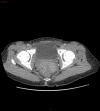

We report the case of a 32-year-old woman who presented with reducible indirect inguinal hernia and a challenging constellation of symptoms, signs and radiographic findings. Surgical approach superseded conservative management when the patient's abdomen became acute, with a rising lactate and haemodynamic instability. Specifically, the presence of a fluid collection was concerning for sinister acute pathology. Our patient was rediagnosed intraoperatively with hydrocoele of canal of Nuck. This so-called 'female hydrocoele' is an eponymous anatomical rarity in general surgery, presenting as an inguinolabial swelling with variable clinical profile. Hydrocoele of canal of Nuck takes origin from failure of transitory reproductive anlagen to regress and is thus analogous to patent processus vaginalis. Its true incidence is speculative, with just several hundred cases globally. We aim to provide insights into surgical patient management for a rare entity during the COVID-19 outbreak, from the unique perspective of a small rural hospital in Scotland.